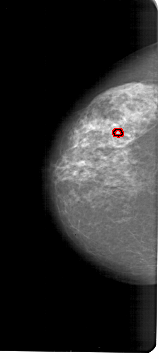

A_1632_1.LEFT_CC

LEFT_CC LINES 6811 PIXELS_PER_LINE 3016 BITS_PER_PIXEL 12 RESOLUTION 43.5 OVERLAY

FILE: A_1632_1.LEFT_CC.OVERLAY

TOTAL_ABNORMALITIES 1

ABNORMALITY 1

LESION_TYPE CALCIFICATION TYPE PLEOMORPHIC DISTRIBUTION CLUSTERED

ASSESSMENT 4

SUBTLETY 2

PATHOLOGY BENIGN

TOTAL_OUTLINES 1